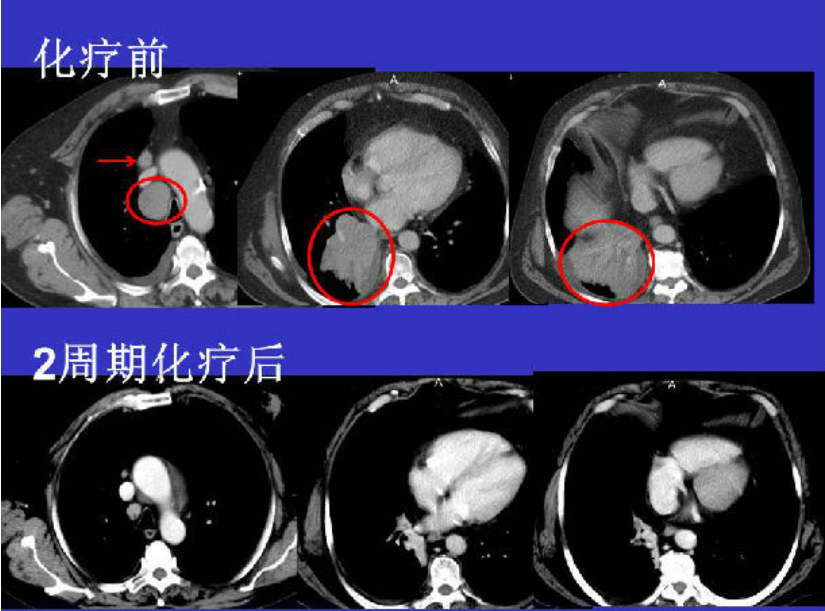

但是小细胞肺癌也有自己的有点,它对化疗和放疗十分敏感,许多小细胞肺癌放化疗后病灶可以接近消失。而且,化疗不仅对于初发的病患有很好的疗效,对于复发的患者化疗也一样可以作为首选治疗。